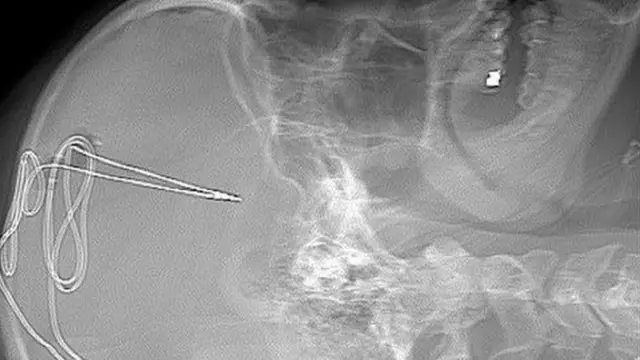

Процес почиње низом скенирања мозга, након чега иде операција током које доктори пацијенту направе рупу у лобањи.

Кроз ту рупу, у тачно одређени део мозга, доктори убаце електроду пречника једног милиметра, чији је задатак да регулише импулсе зависности и самоконтролу код пацијента.

Електрода има и батерију, која се уграђује испод кључне кости.